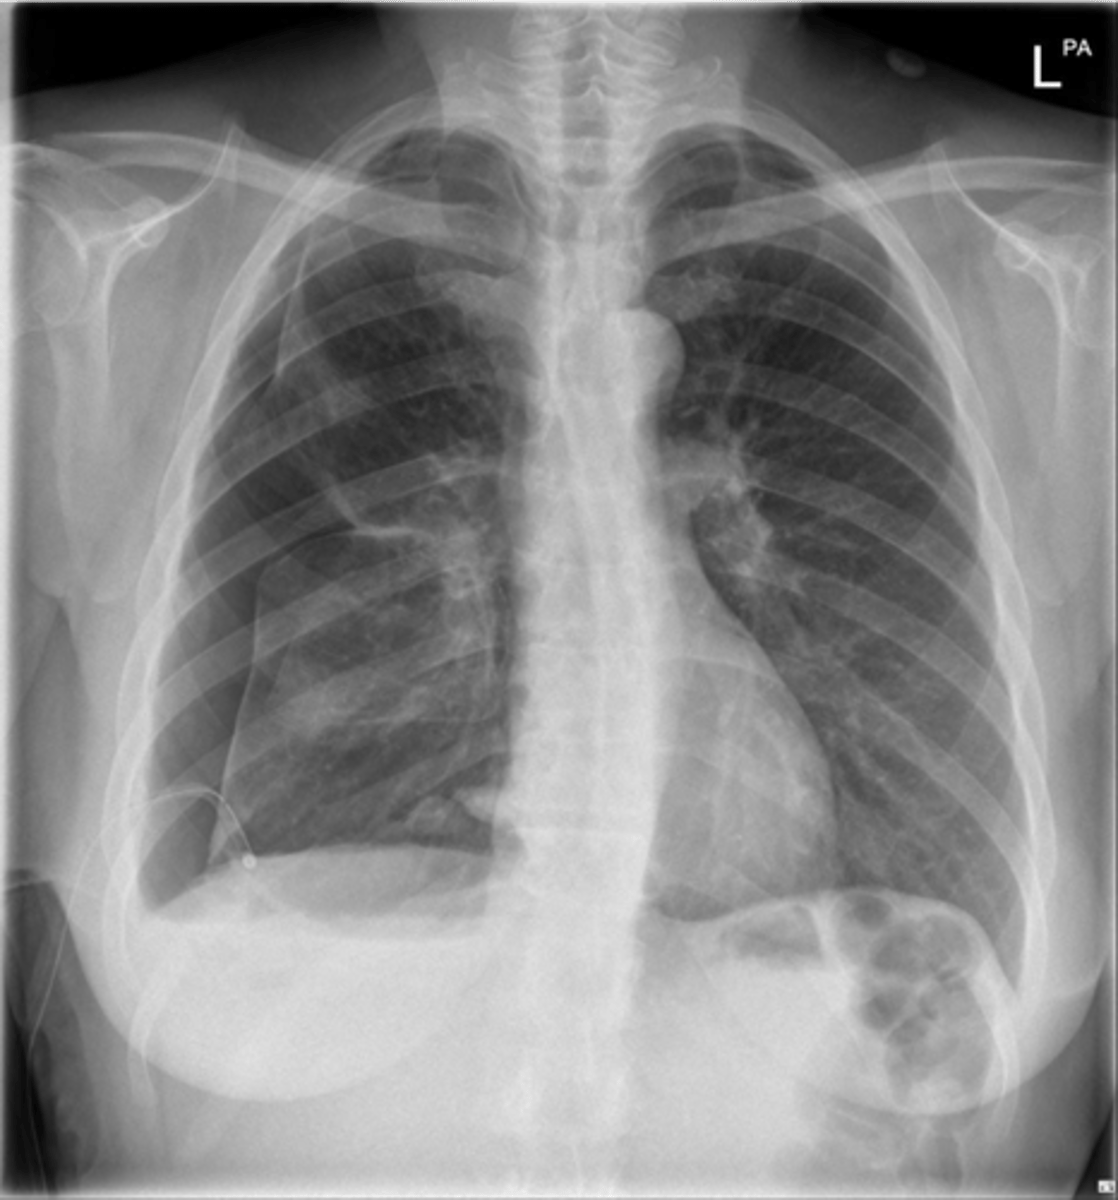

congestive heart failure

knowt flashcard image